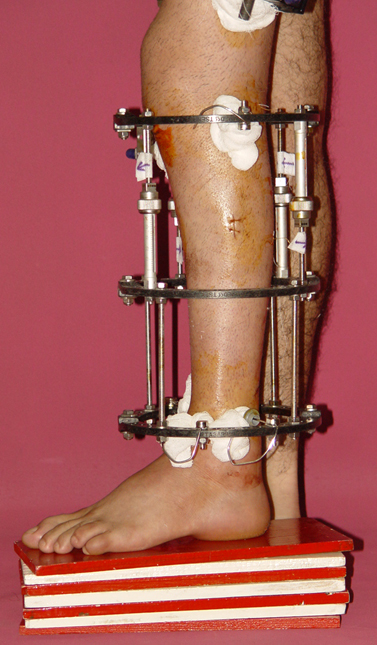

3- POSTTRAVMATİK BACAK KISALIĞI (YANLIŞ KAYNAMA)

Bu Bacak Kısalık tipi bir kırığın kısalmış pozisyonda kaynaması ile oluşur. Bir çok vaka yetişkinlerde görülür ve sadece bir uzatma ile tedavi edilebilir. Ek deformiteler de aynı anda düzeltilebilir. Bu hastaların çoğu çivi üzerinden uzatma veya tam implante edilen çivi ile tedavi edilebilirler.